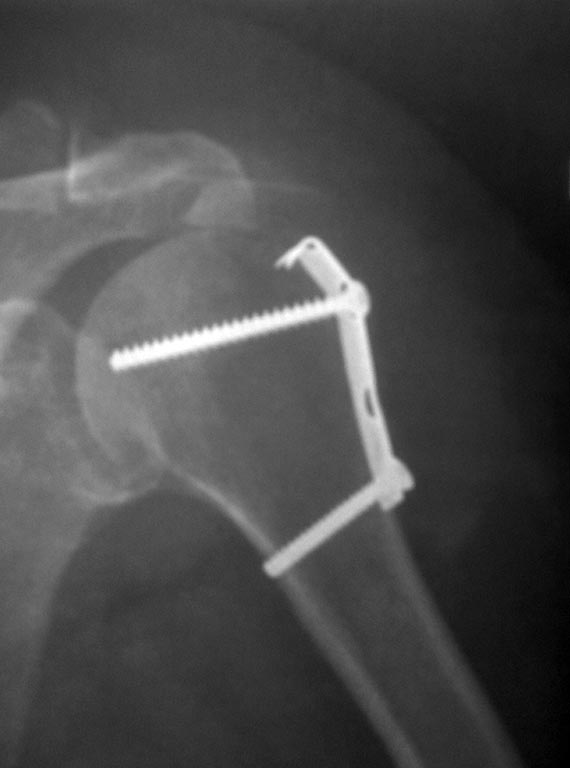

Коллеги! Подскажите, пожалуйста марку металла и фирму производителя представленной металлоконструкции!

По понятным причинам возникла необходимость в МРТ и лучевых диагностов интересует этот вопрос. Пациентка оперирована в другой больнице. Заранее признателен!

То, что фрагмент большого бугорка надо возвращать на место, очевидно даже по этой одной картинке не самого лучшего качества.

Фирму-производитель установить нереально, да и незачем - это треть-трубчатая пластинка, которые делают буквально все. Есть и стальные, и титановые.

Спасибо, Андрей Петрович! Удалось выяснить, что это нержавеющая сталь, фирма ChM!

Александр Николаевич, вполне с Вами согласен, но на необходимости МРТ настаивали специалисты Праги! "В своём отечестве пророков нет"!. Предположили, что это может быть и известковый субакромиальный бурсит, хотя демонстрируемая рентгенограмма сделана непосредственно после операции, где четко просматриваются и кортикалис и спонгиоза отдельно лежащего отломке большого бугорка! Спасибо!